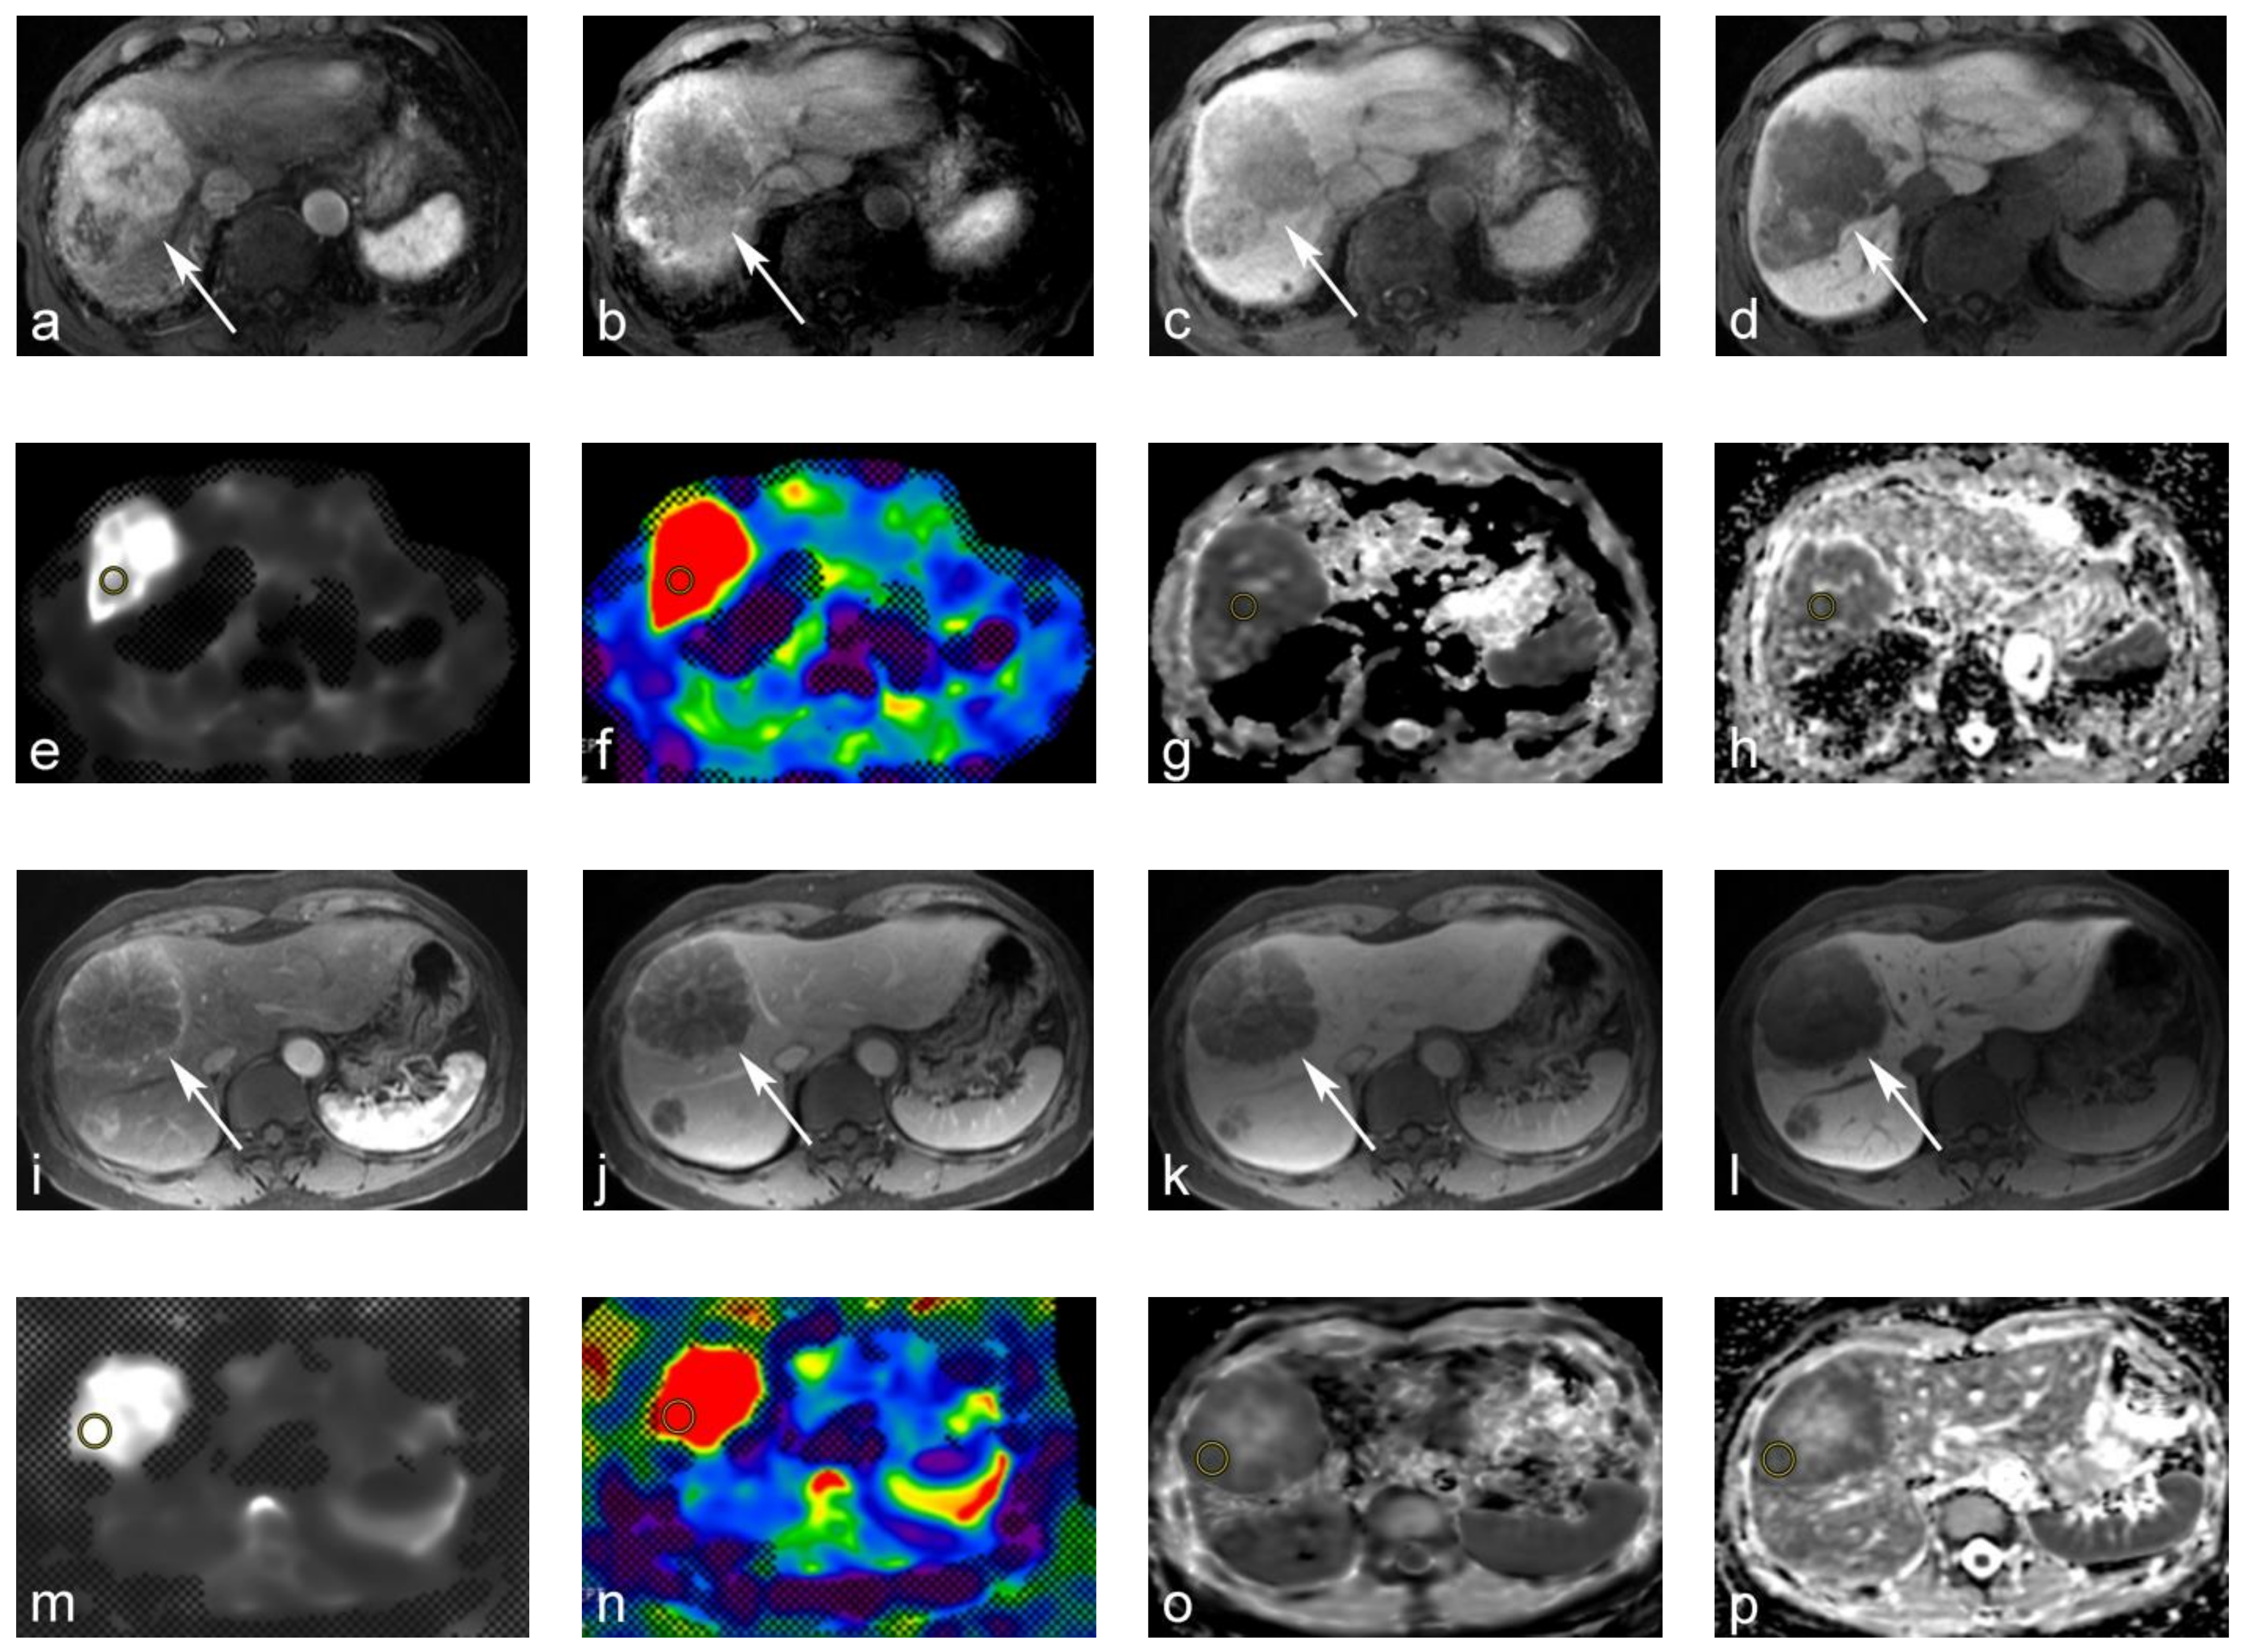

Figure 2.

69-year-old male with moderately differentiated hepatocellular carcinoma (HCC). (a–d) Gd-EOB-DTPA-enhanced magnetic resonance image (MRI): (a) tumors show arterial hyperenhancement on the arterial-phase. (b,c) Tumor shows a washout on the portal venous and transitional phase; (d) tumor shows a hypointensity on the hepatobiliary phase. (e,f) MR elastography (MRE). The tumor yielded a stiffness of 10.71 kPa on the MRE. (g,h) Apparent diffusion coefficient (ADC) maps. The tumor yielded a value of 0.63 × 10−3 mm2/s on the shifted ADC (sADC) map, and a value of 0.93 × 10−3 mm2/s on the ADC map. 60-year-old male with metastatic hepatic cancer from colorectal cancer. (i–l) Gd-EOB-DTPA-enhanced MRI. (i,j) Tumor showed rim-like enhancements on the arterial and portal venous phase. (k,l) The tumor was hypointense on the transitional and hepatobiliary phases. (m,n) MRE. The tumor yielded a stiffness of 15.59 kPa on MRE. (o,p) ADC maps. The tumor also yielded an sADC value of 0.72 × 10−3 mm2/s on the sADC map, and 0.86 × 10−3 mm2/s on the ADC map.